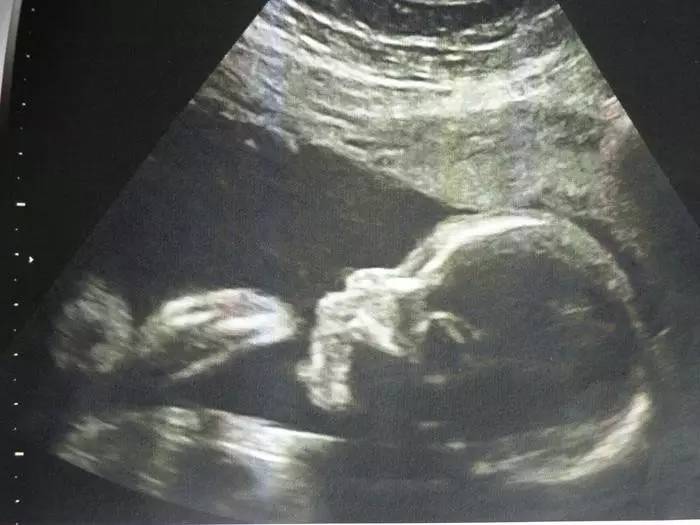

正常胎儿超声测量有许多的指标,在妊娠不同时期,可靠的测量指标有所不同,比如:孕12周以前,头臀长测量孕周最可靠;在孕12-24周时,双顶径测量值最可靠;孕28周以后,头围测量值最可靠;分娩前几周,通过胎儿的腹围测量推测胎儿体重最可靠,当胎头过大或颅内有病变时,股骨的测量值较可靠。测量这些数值与B超医生的技术有很大关系,与机器的质量也有关系,只有标准切面的测量值,才能提供标准的胎龄与体重。

最常测定的径线有头臀长(CRL)、双顶径(BPD)、头围(HC)、腹围(AC)和股骨长(FL)、肱骨长(HL)、尺骨长(UL)、径骨长(TL)、锁骨长(LL)及眼距(BN)等。

中晚期妊娠的超声测量

股骨(FL)

它的正常值与相应的怀孕月份的BPD相差2-3mm左右,一般在妊娠20周左右,通过测量FL来检查胎儿发育情况。